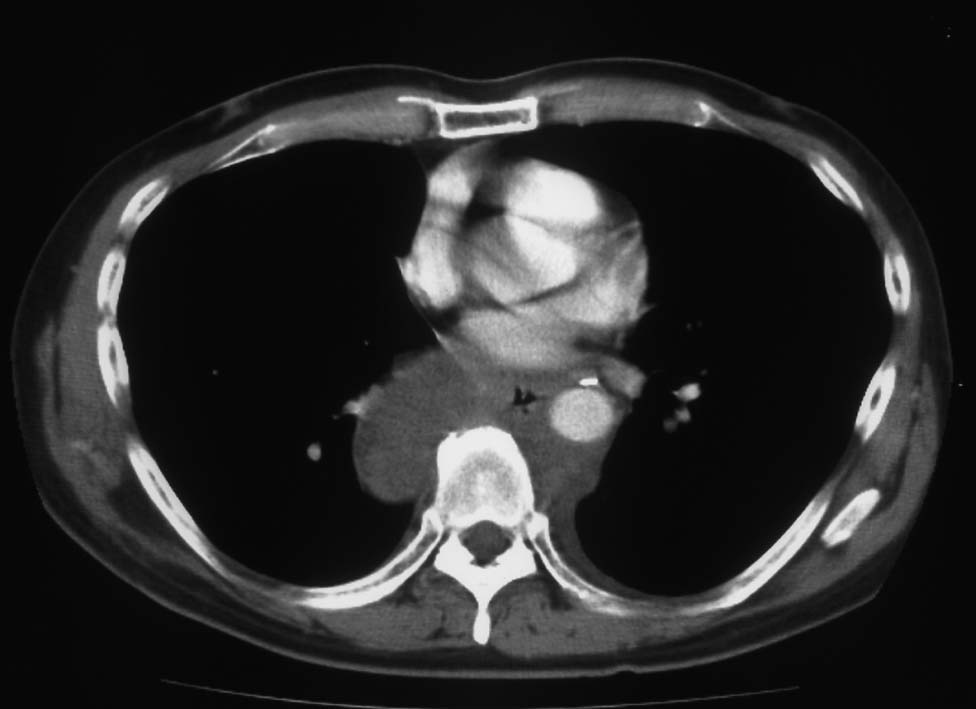

5ヵ月後右主気管支を圧迫しほとんど閉塞する巨大な腫瘍を認めた. 他院で緊急放射線療法および化学療法を行うが効果なし. 腫瘍切除+右肺上葉切除をおこない肉眼的には腫瘍は完全切除できた. 病理診断は非典型的であるが malignant SFT. 当院に再入院, radiation therapyをおこなう. 効果乏しく, 腫瘍は進行し呼吸不全で永眠される.

胸腔鏡下ブラ切除術5ヵ月後, 縦隔腫瘤で再発. 他院で腫瘍切除+右肺上葉切除を施行. 肉眼的には腫瘍は完全に切除できた.